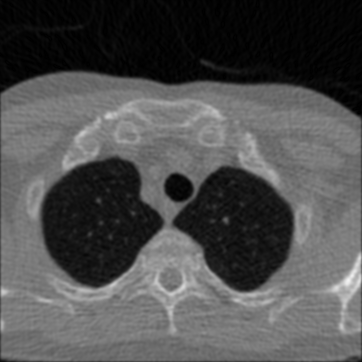

5.5.3 Results

In Figure 12 we compare the PD3O reconstructions (top) and their corresponding errors with respect to the ground truth (bottom) using different regularization parameter choices , and for PD3O. Obviously, using the estimated parameter-map leads to a significant improvement of the reconstruction. In particular, sharp edges are retained, while using a constant regularizing parameter results in a significant blur. This can be also seen in Table 4, where we compare the NRMSE, PSNR, SSIM and blur and evaluated on the first 100 test images of the LoDoBaP dataset. These results are visualized in Figure 13 using box-plots. Note that the FBP seems to better than PD3O- in terms of the blur effect, but this can be explained by the fact that FBP reconstructions admit a lot of high-frequency artefacts leading to a small blur effect.

Further PD3O- reconstructions with their corresponding estimated parameter-maps are shown in Figure 14. Note that the parameter-maps are given in a logarithmic scale. As expected, the regularization is strong in constant areas and less strong on edges or finer details in order to reduce a smoothing in these regions.